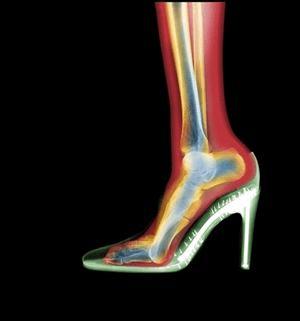

美丽的脚